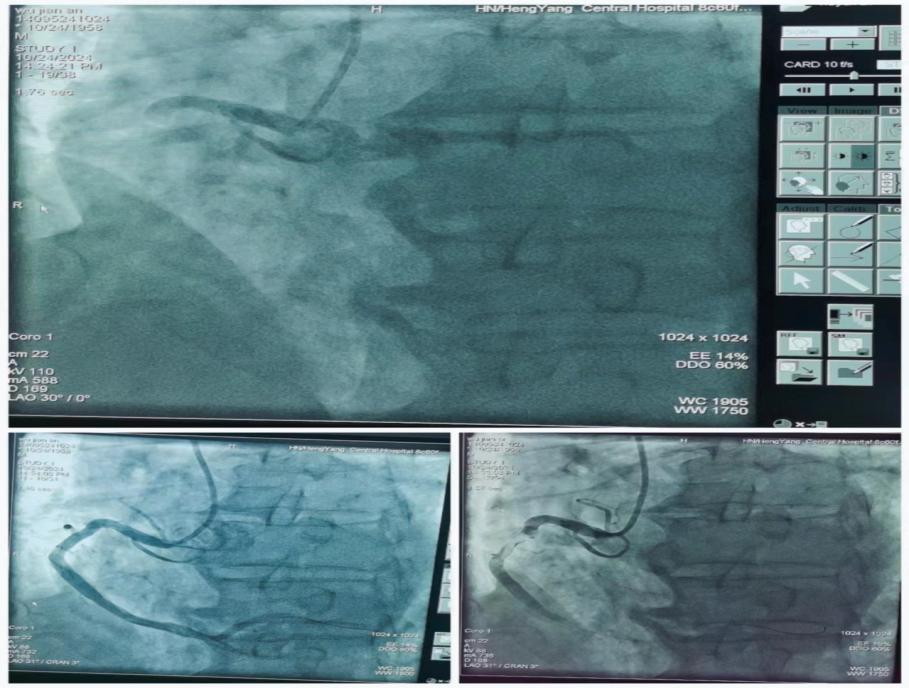

心內(nèi)科朱曉宇主任醫(yī)師急會診后,考慮Kounis綜合征-過敏性急性冠脈綜合征。與家屬溝通病情立即啟動急性心梗急救流程,開通胸痛綠色通道送入導(dǎo)管室行急診PCI。急診冠狀動脈造影顯示右冠第一轉(zhuǎn)折后完全閉塞并大量血栓影,賓建國副主任醫(yī)師帶領(lǐng)介入團(tuán)隊行急診右冠內(nèi)血栓抽吸+PTCA+支架植入術(shù),手術(shù)時間約40分鐘,術(shù)后病人安返心內(nèi)科病房。